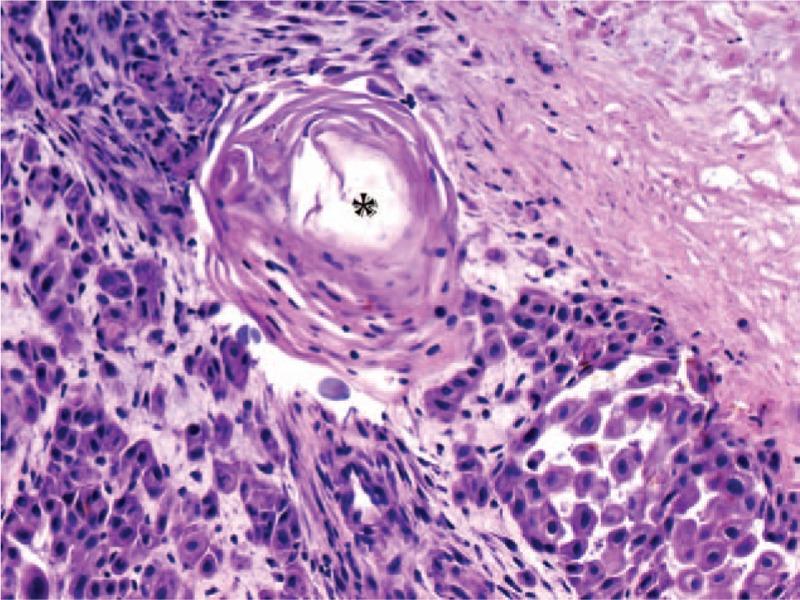

Primary vaginal squamous cell carcinoma (SCC) is a rare disease. Primary SCC in prolapsed vagina is extremely rare. In the presented case additional bladder involvement was found.

Diagnosis was confirmed by the vaginal ulceration biopsy and cystoscopic biopsy of the involved bladder.

Primary SCC mimicking decubitus which appeared in prolapsed vagina, may be accompanied by bladder involvement.

原发性阴道鳞状细胞癌(SCC)是一种罕见疾病。脱垂阴道中的原发性SCC极为罕见。在本病例中,发现了额外的膀胱受累情况。

通过阴道溃疡活检和受累膀胱的膀胱镜活检确诊。

模仿脱垂阴道中褥疮出现的原发性SCC,可能伴有膀胱受累。